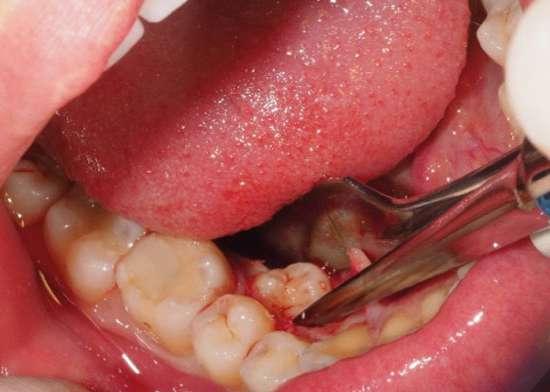

A la exploración intraoral se observaba abombamiento de la cortical lingual en la zona derecha de la mandíbula (Fig. 1). Se realizó un CBCT donde se pudo observar que el diente supernumerario tenía aspecto de premolar, estando alojado de manera

cabalgada entre lingual y vestibular (la corona del diente se encontraba por la zona linguodistal del 44, mientras su raíz se localizaba a nivel interradicular, en íntimo contacto con el nervio dentario inferior.

Dada la cercanía a las raíces de los dientes adyacentes y el riesgo de rizólisis de las mismas, se optó por realizar la exodoncia, utilizando para ello anestesia local de la zona (Fig. 2).

Tal y como se puede observar en las imágenes (Fig. 3 y 4) se realizó una incisión sulcular siguiendo el surco gingivodentario lingual sin descargas para despegar un colgajo a espesor total que facilitó un campo quirúrgico suficiente como para poder realizar la ostectomía hasta descubrir la corona del diente (Fig. 5).

La ostectomía se realizó de manera cuidadosa, tanto con el colgajo y las estructuras del suelo de boca, como con los dientes adyacentes y sus raíces. En este caso el diente no requirió odontosección, por lo que su exodoncia pudo ser completada usando un botador recto y unas pinzas adson para su retirada del alveolo (Fig. 6).

Figuras 1 y 2. Situación inicial y anestesia. Figuras 3 y 4. Incisión y despegamiento del colgajo lingual festoneado.

Figuras 5 y 6. Ostectomía y exodoncia con botador tipo elevador recto.